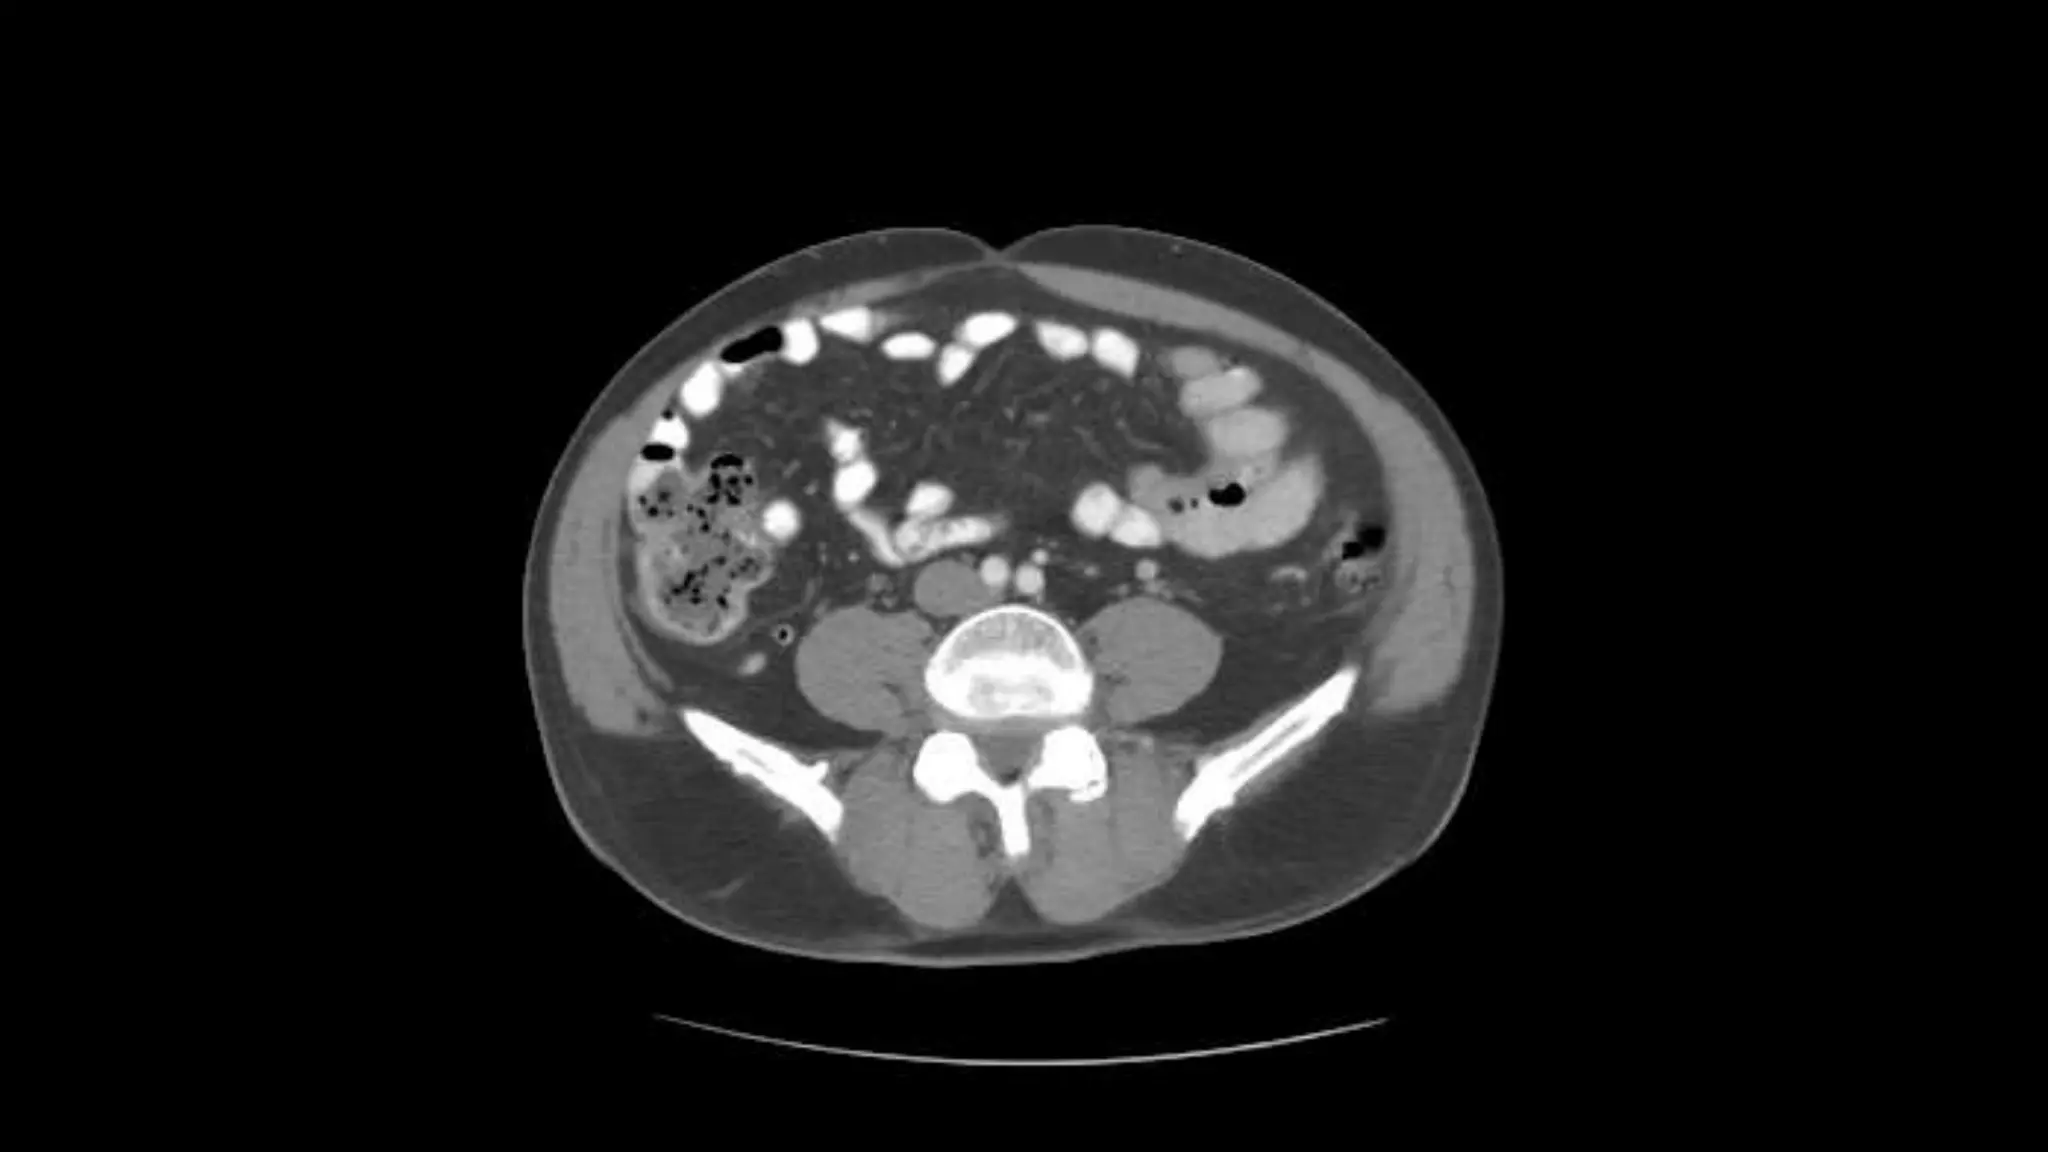

Renal Veins emptying into the IVC. We also see the right renal artery branching

off the Aorta, follow it down till you see it enter the right kidney. The Superior

Mesenteric Vein is outlined on the top of this image. If you follow the SMV up, you

will see it empty into the Portal Vein.

Here we see the right and left renal vein entering into the Inferior Vena Cava. We

Also see the left renal artery branching off the aorta and heading toward the left

kidney. Page up and down to trace these vessels.